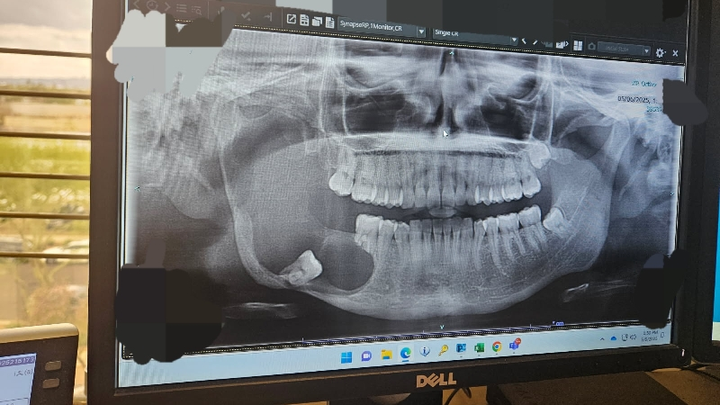

I am raising money for surgery expenses. I met with the surgeon yesterday to go over the latest scans on the tumor in my jaw. Now we're on a deadline to remove it before it reaches my skull base.

My jaw has eroded from the tumor/infection and they will need to remove bone from my leg to rebuild my jaw.